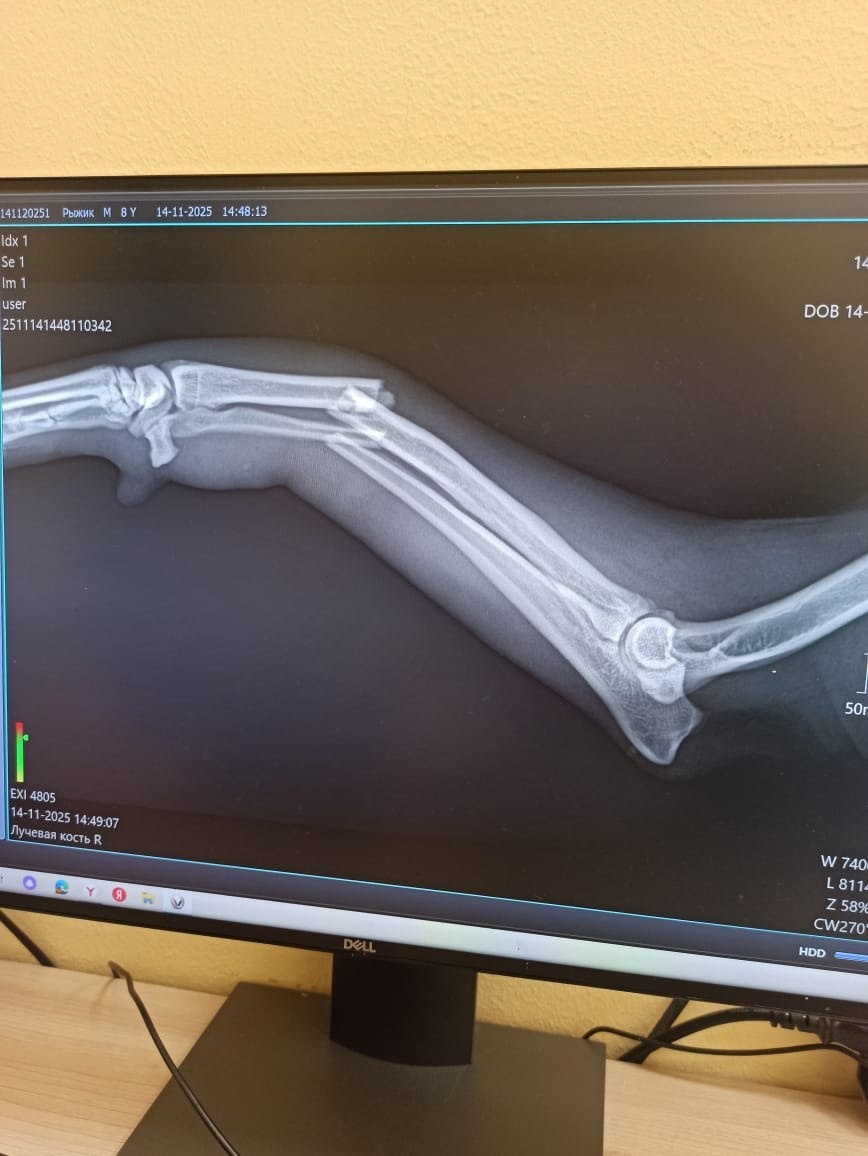

Рыжик, парню лет 5 плюс минус год. Подкинули в городок пару лет назад, так там и обитал, пока с ним не приключилась беда , непонятным образом сломал лапу, так и проходил два дня, пока его не поймала и не отвезла в клинику.

Провели операцию, оплатили совместными усилиями. Впереди лечение и долгое восстановление, на улицу нельзя. Плюс у него обнаружилось воспаление простаты, моча не отходит полностью, подтекает, оставляя лужицы. Поставили катетер, будут сцеживать мочу, пока мочевой не заработает как надо. Далее предстоит лечение и долгое восстановление на платной передержке , которое займёт несколько месяцев. Нужна финансовая поддержка, а лучше финкураторство до восстановления! Хотя бы оплачивать передержку Рыжика . Он сидит на передержке с другом , за которого тоже надо платить , двоих не потяну собак, а реабилитация долгая.